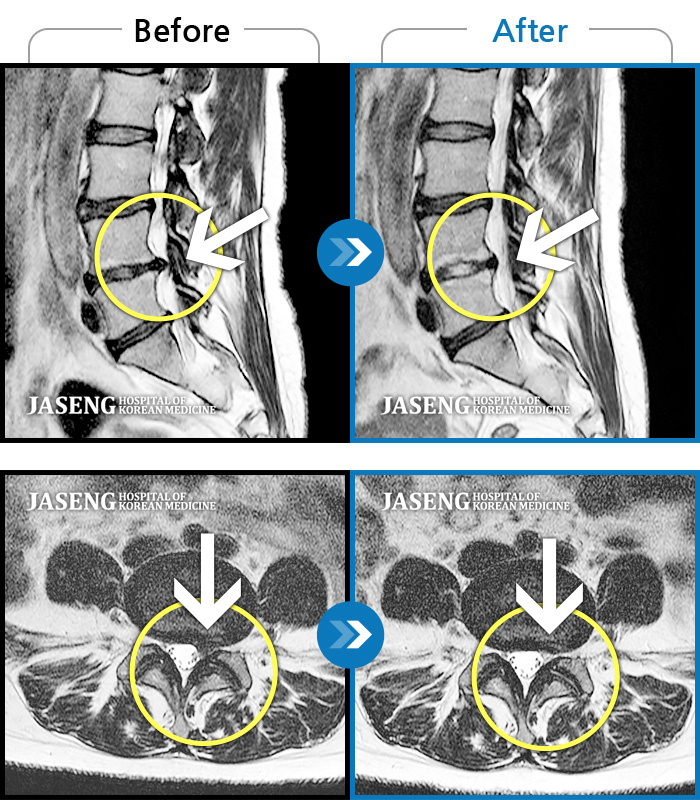

Before

After

환자에게 사전 동의를 받아 동일 조건에서 촬영되었습니다.

개인에 따라 치료 후 부작용이 발생할 수 있으니 의료진과 상담 후 치료를 진행하시기 바랍니다.